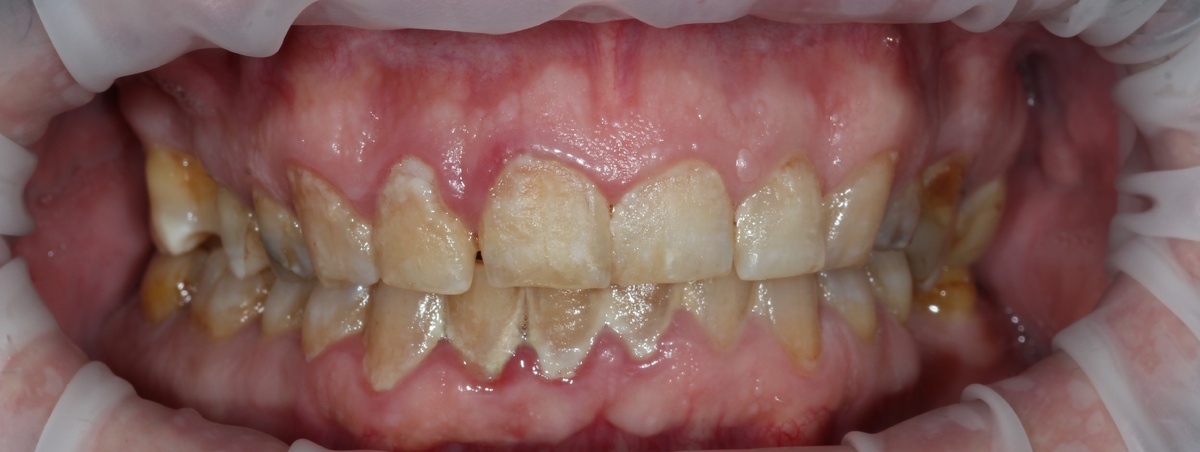

После

Между визитами прошло 7 месяцев — это в два с лишним раза больше стандартного интервала!

И что мы увидели при повторном визите?

• ✅ Минимальное количество мягкого налета

• ✅ Здоровые десны без признаков воспаления

• ✅ Отсутствие зубного камня

• ✅ Идеальное состояние проблемных зон

• ✅ Уверенность пациента в правильности домашнего ухода

Для сравнения: обычно после стандартной гигиены без обучения состояние полости рта ухудшается уже через 2-3 месяца.